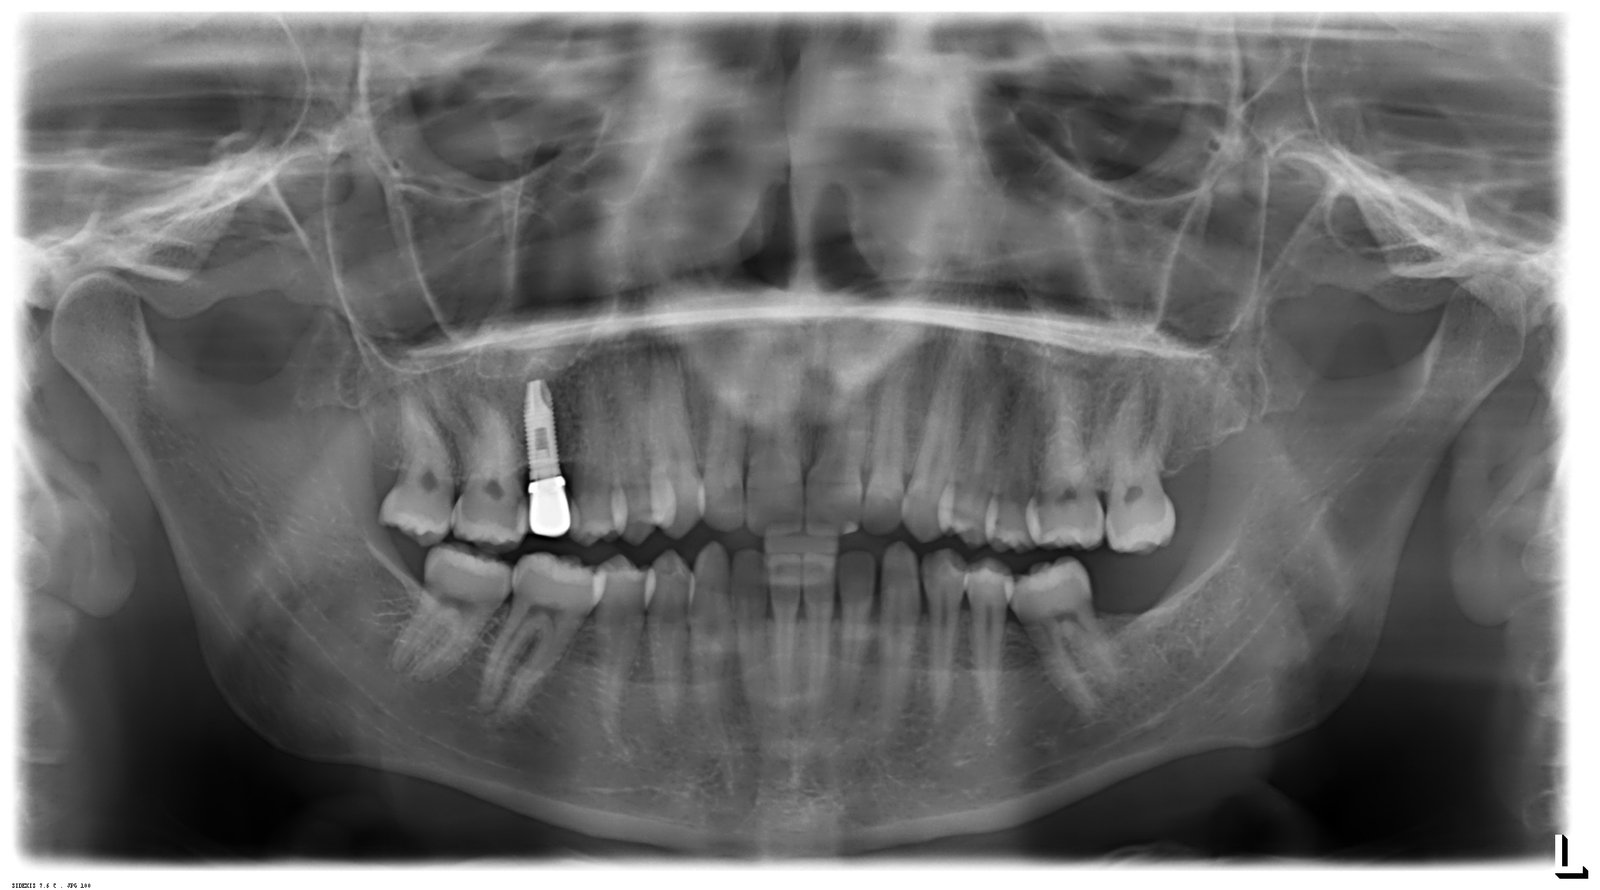

Buenos días, necesitaría saber que implate es este. Se lo han puesto hace unos meses en la Universidad Complutense y no sabe ni marca, conexión, plataforma,etc ¡gracias!